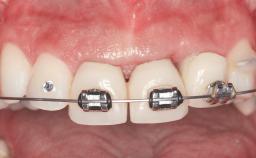

Replacement of Four Incisors with a Fixed Partial Denture on Two Narrow-Neck Implants after Implant Failure

| Prosthesis Type | FDP |

| Defining Characteristics | Up to three missing teeth to be replaced with an implant-borne restoration or restorations |

| Retention | Screw-retained, with splinted implants Screw-retained, with splinted implants |